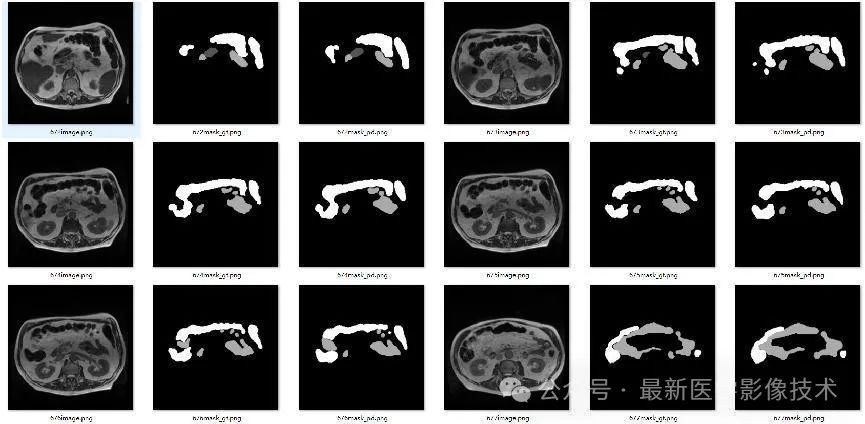

4、验证集部分分割结果